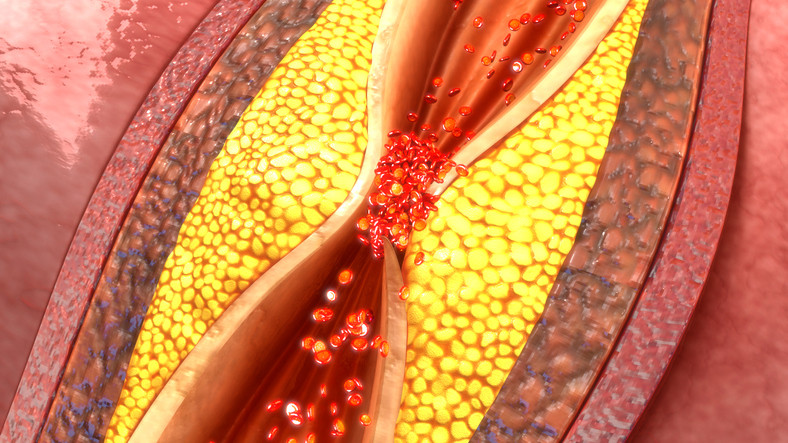

أمراض وأعراض 1 دقائق الذبحة الصدرية: فهم شامل لأمراض القلب وأعراضها وطرق الوقاية تعتبر الذبحة الصدرية من أخطر أمراض القلب التي تؤثر على حياة الملايين حول العالم، وتُعد مؤشراً على وج...